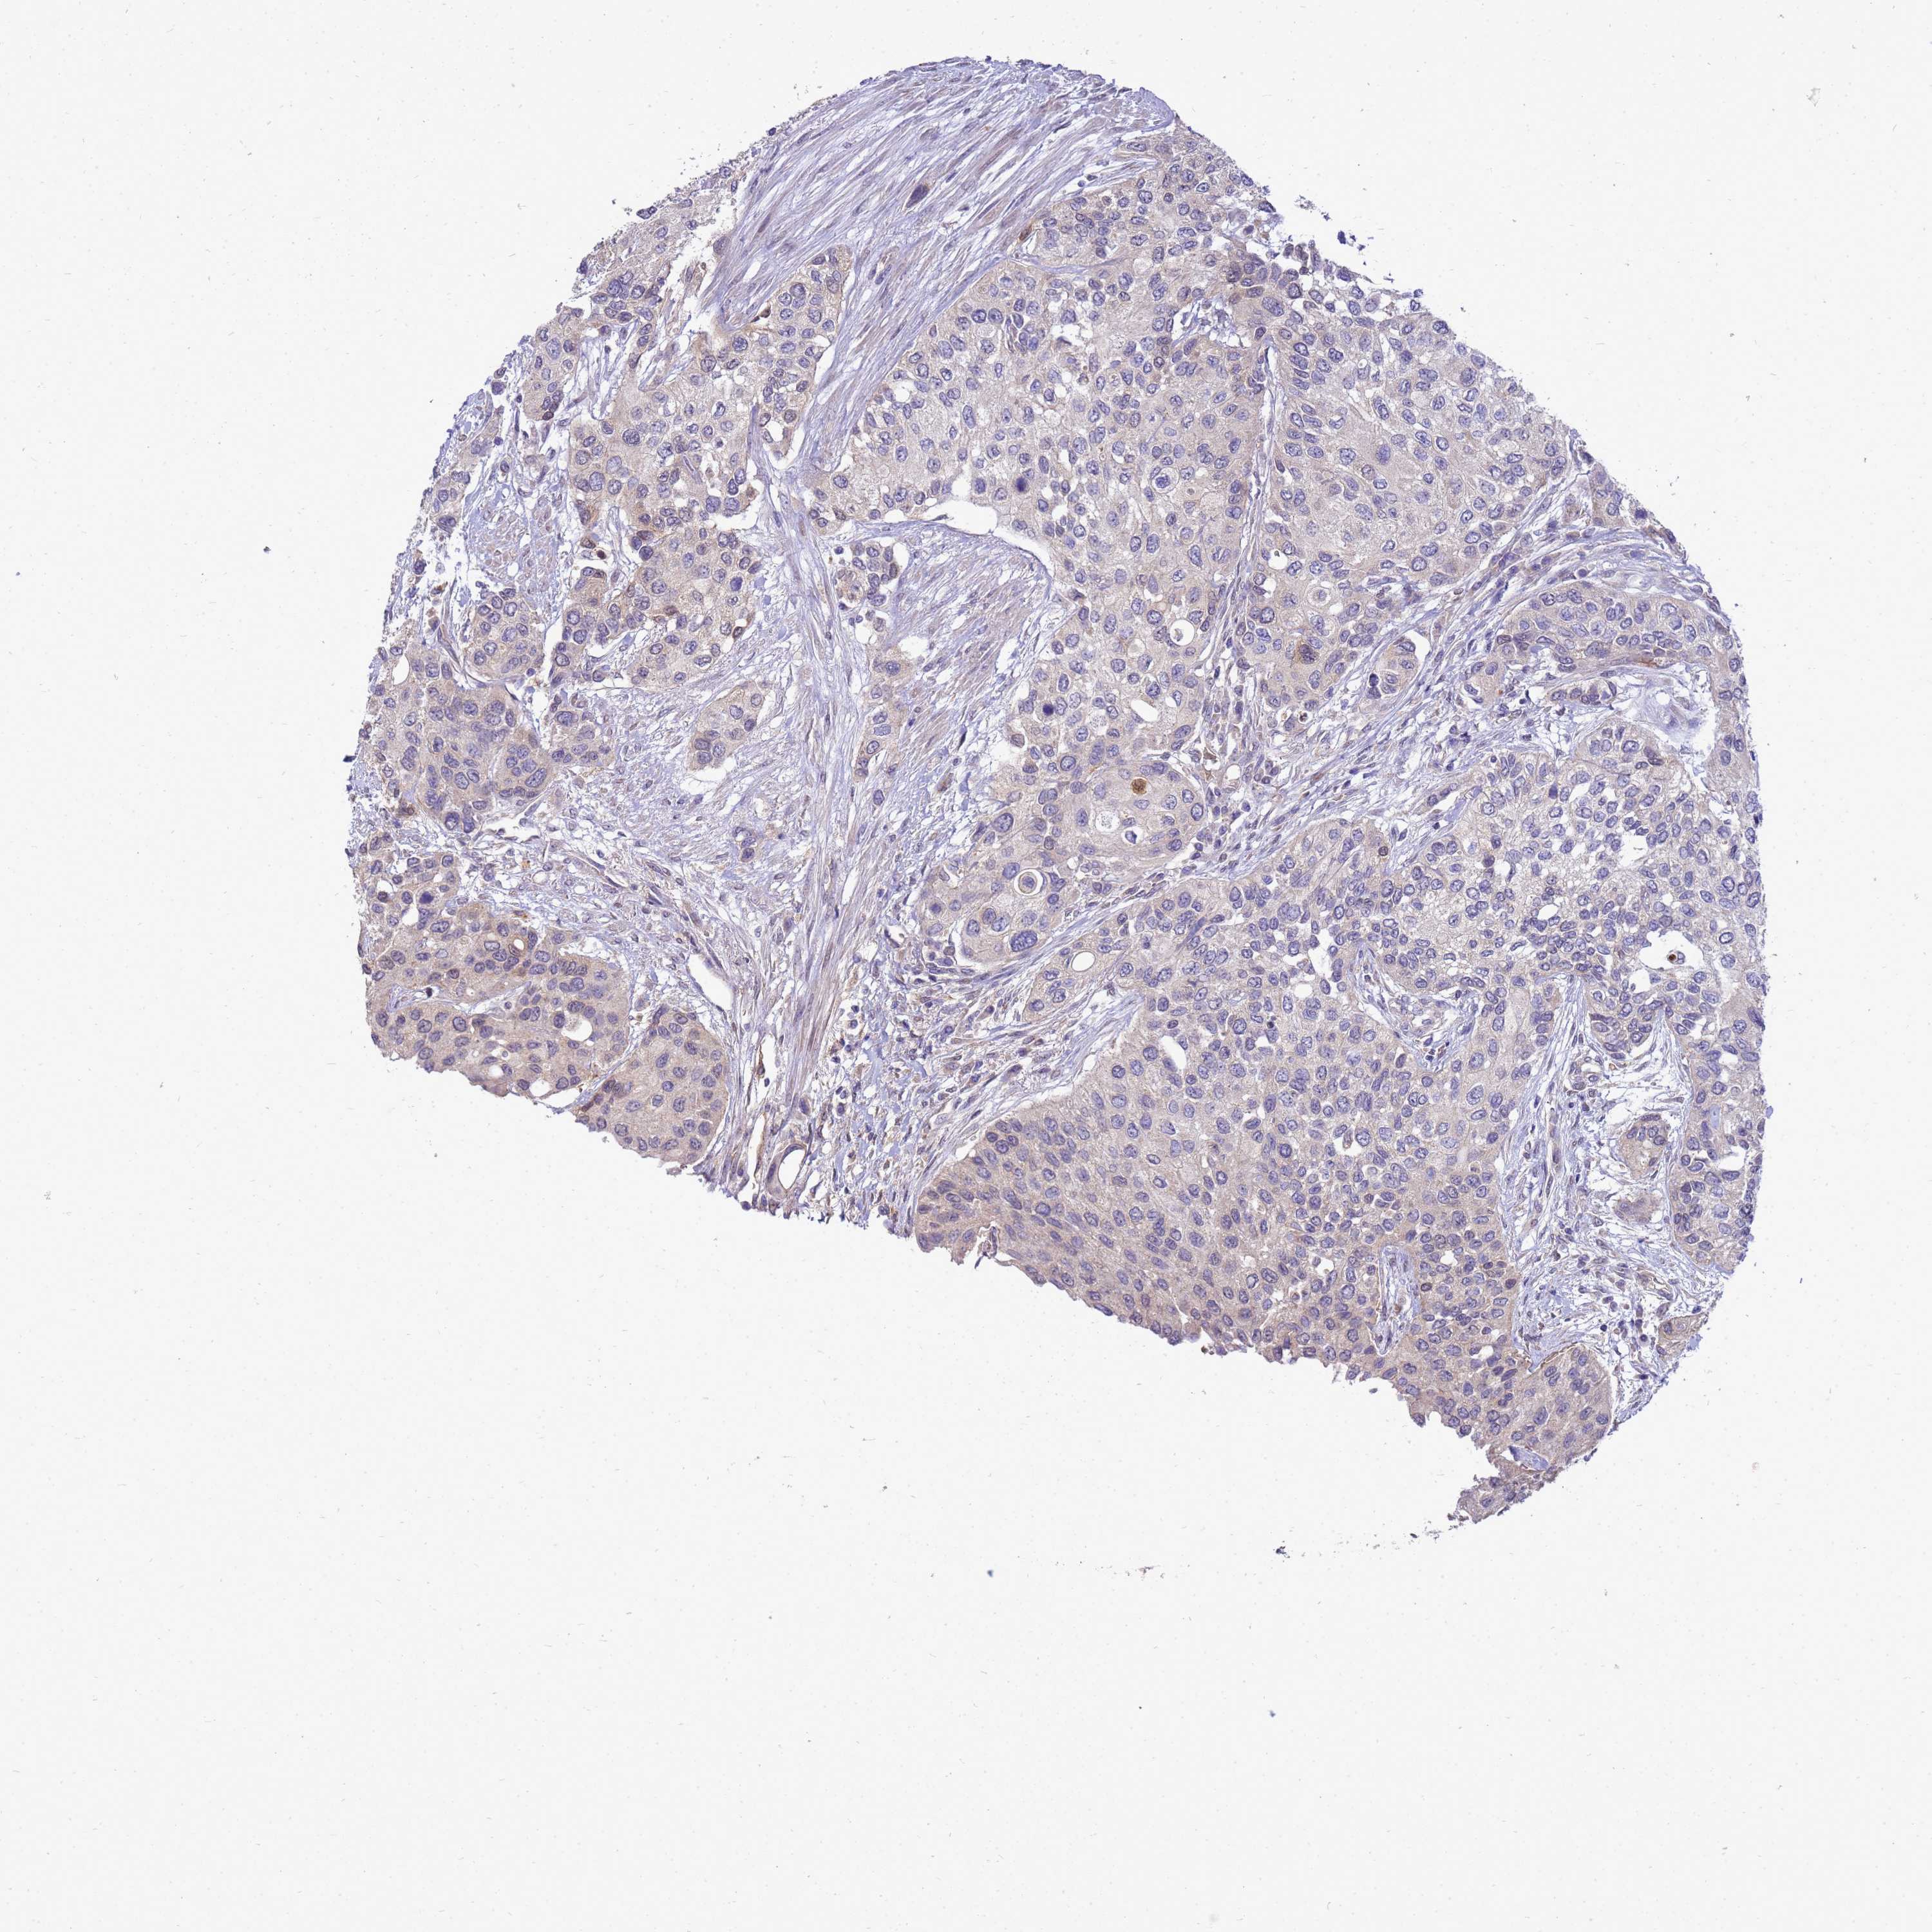

UROTHELIAL CANCER - Protein expressioni

A mouse-over function shows sample information and annotation data. Click on an image to view it in a full screen mode. Samples can be filtered based on level of antibody staining by selecting one or several of the following categories: high, medium, low and not detected. The assay and annotation is described here.

Antibody stainingi

Antibody staining in the annotated cell types in the current human tissue is reported as not detected, low, medium, or high, based on conventional immunohistochemistry profiling in selected tissues. This score is based on the combination of the staining intensity and fraction of stained cells.

Each image is clickable and will lead to virtual microscopy that enables deeper exploration of all samples and also displays staining intensity scores, fraction scores and subcellular localization as well as patient and tissue information for each sample.

Antibody HPA045537

Staining

High

Medium

Low

Not detected

Intensity

Strong

Moderate

Weak

Negative

Quantity

>75%

75%-25%

<25%

None

Location

Nuclear

Cytoplasmic/membranous

Cytoplasmic/membranous,nuclear

Urothelial carcinoma, High grade

Urothelial carcinoma, Low grade

Urothelial carcinoma, NOS